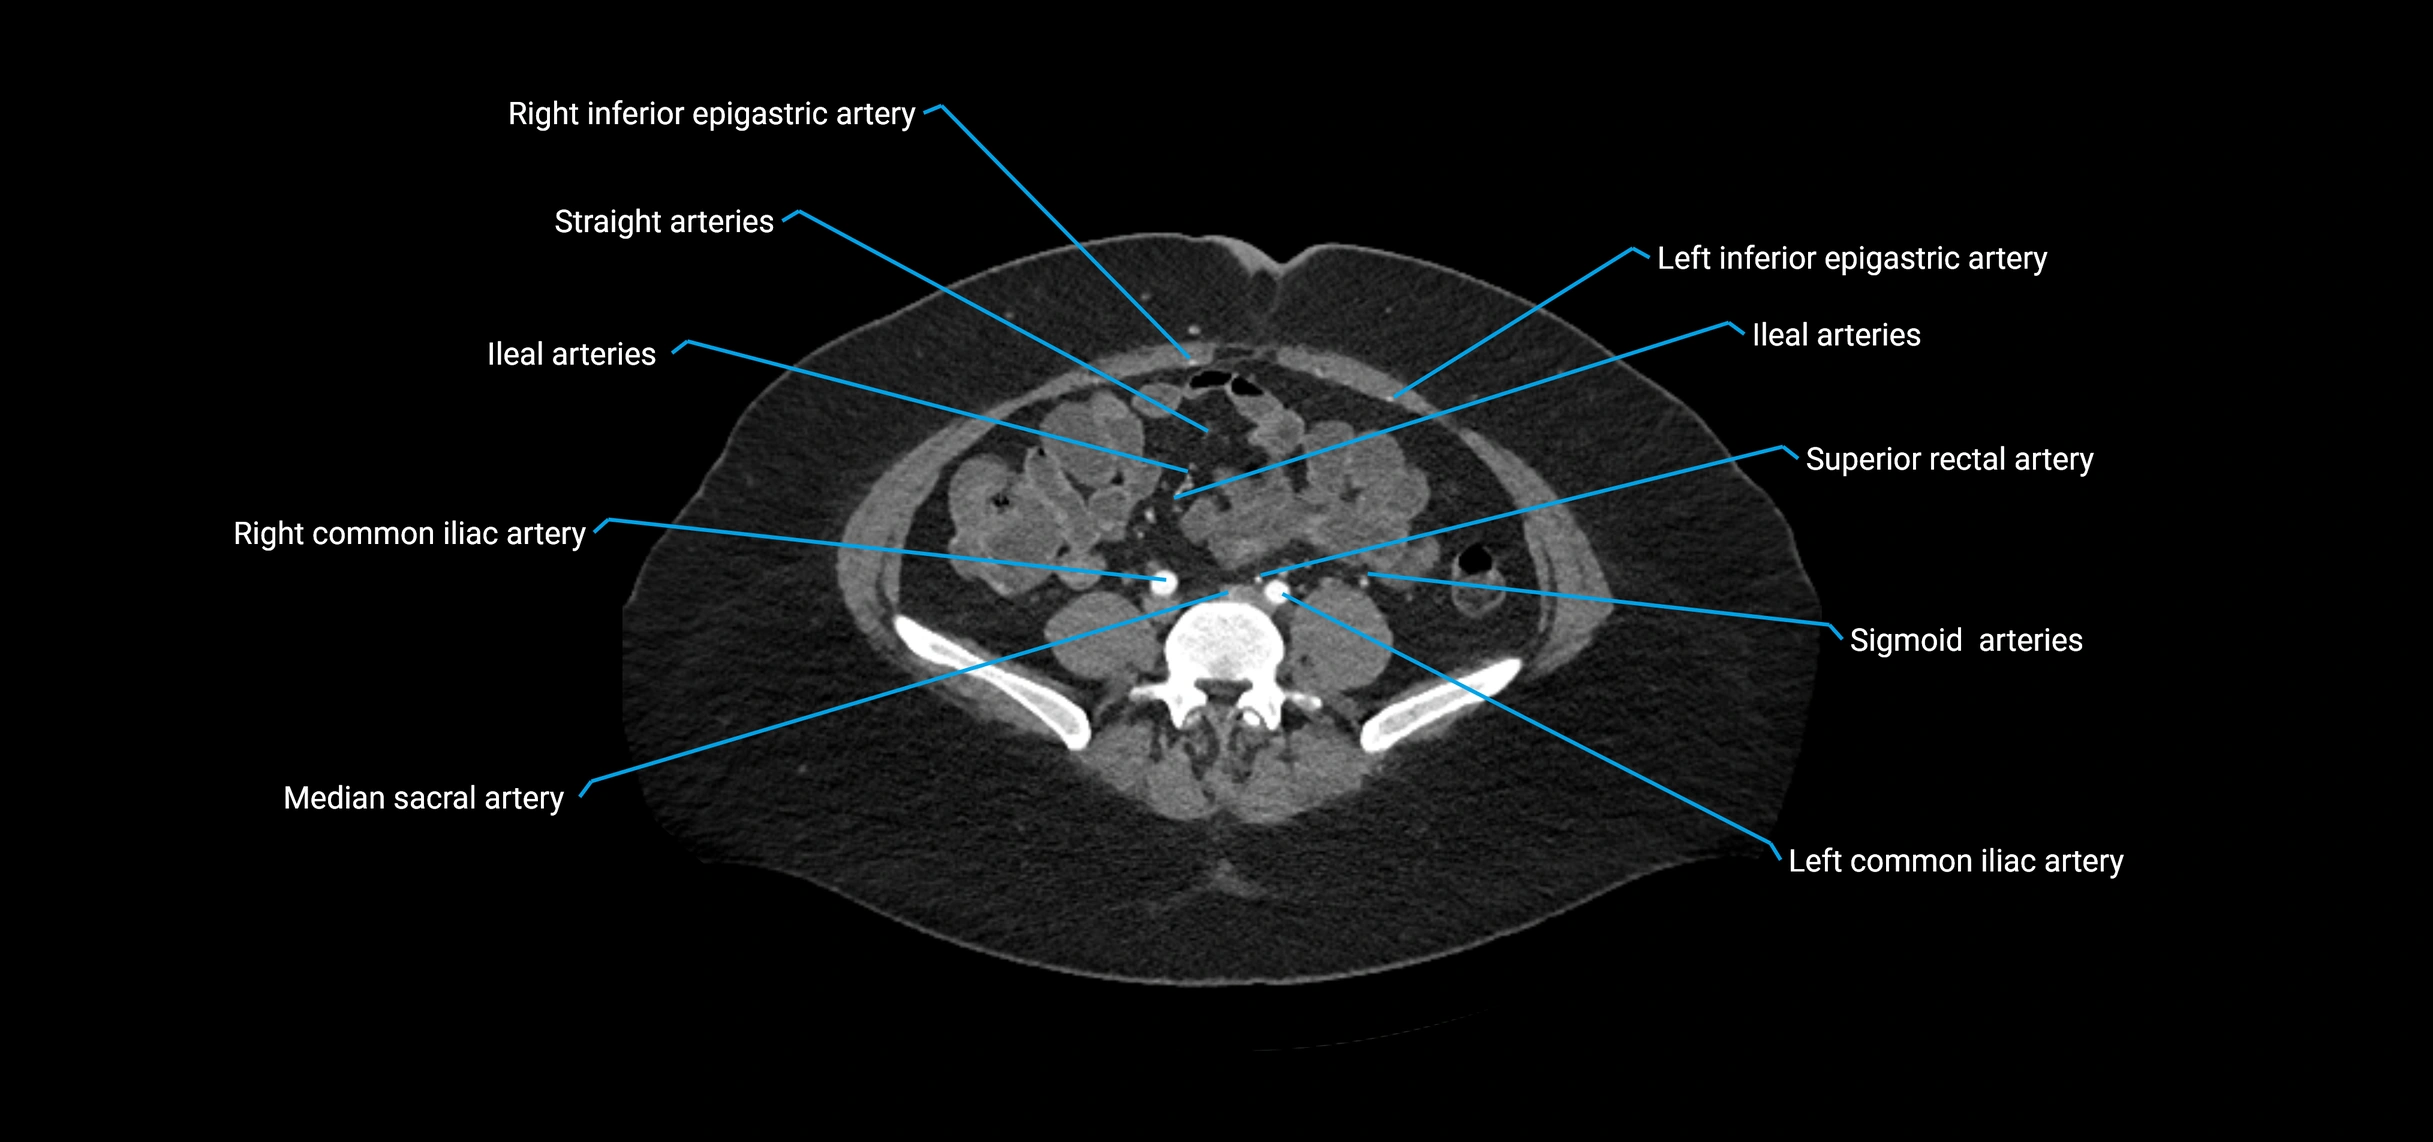

Contrast-enhanced CT (CTA):

• Gold standard for abdominal aortic imaging

• Provides excellent detail of lumen, wall, aneurysm, thrombus, and branch vessels

• Multiplanar and 3D reconstructions help in aneurysm measurement, stent graft planning, and dissection evaluation

• Detects acute rupture, traumatic injury, or occlusion with high sensitivity